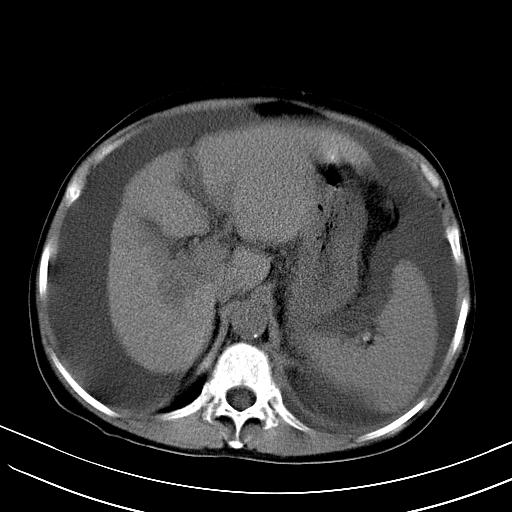

标题: CT23697:肝癌并肝动静脉漏? [打印本页]

标题: CT23697:肝癌并肝动静脉漏?

1)肝右叶肝癌并肝动静脉漏。2)肝硬化,腹水。3)胆囊炎。

肝右叶肝癌并动静脉漏,肝硬化,腹水。

1)肝右叶肝癌并肝动静脉漏 门v右支瘤栓伴海绵样变。2)肝硬化,脾大 腹水。3)胆囊炎。门v高压.

右叶肝癌并肝动静脉漏(动脉期肝动脉及门静脉内均可见造影剂),肝硬化,腹水。(胆囊壁水肿)

1)肝右叶肝癌,考虑并发肝动静脉漏。扫描时间好像慢了。2)肝硬化,门脉高压、脾大、腹水。